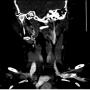

CTA showing tortuosity of right extracranial ICA at level C2 (white arrow)

Case Report Page 805 - 810

Unilateral Pulsatile Tinnitus in Young Female Adults: A Report of Two Cases